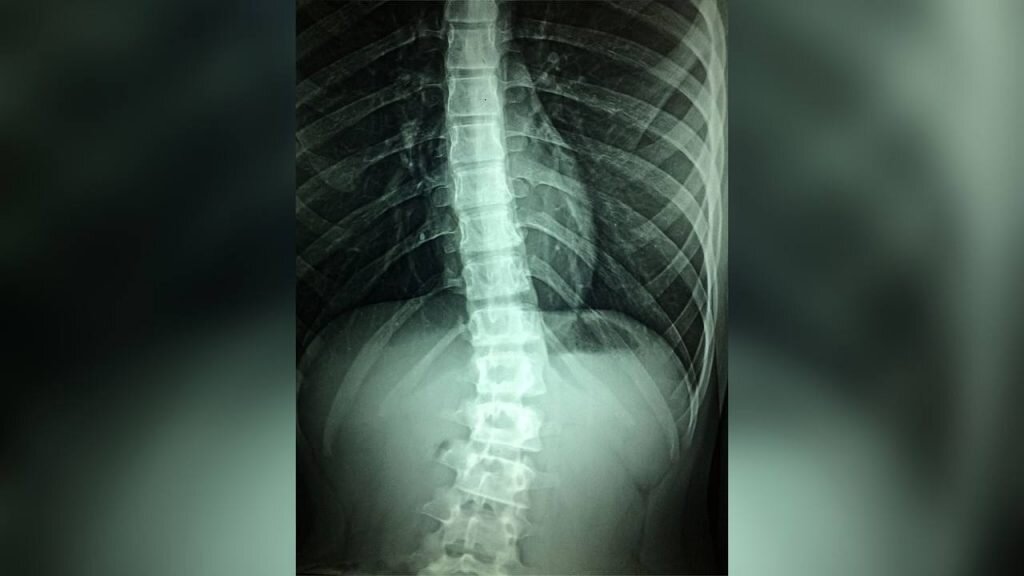

Новые наночастицы могут предотвратить паралич из-за травмы спинного мозга

Наночастицы, наполненные противовоспалительным препаратом, уменьшают повреждение после травмы спинного мозга.

Исследователи разработали наночастицы, которые затем наполнили лекарствами. Они избирательно воздействуют на клетки, которые вызывают воспаление процесса после травмы спинного мозга. Терапию уже опробовали на мышах. Она уменьшила воспаление и улучшила двигательную функцию.